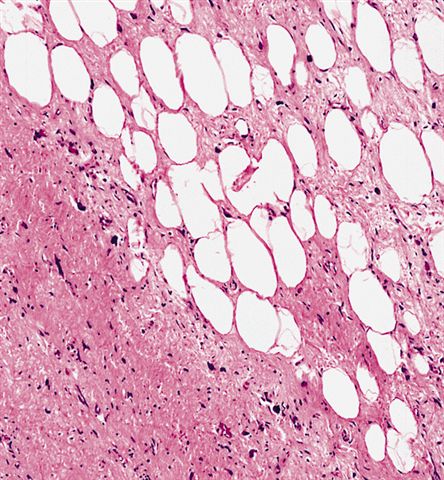

Contributed by Michael Clay, M.D., Melanie Bourgeau, M.D. and AFIP

Morphologic variability:

- Lipoma-like subtype

- Most common subtype

- Scattered atypical cells may be diffuse or exceedingly rare

- Frequently contains lipoblasts

- Grossly, can be indistinguishable from lipoma

- Depends on subtype, generally composed of mature fat with variably sized adipocytes and bands of fibrotic stroma containing spindle cells with enlarged, hyperchromatic nuclei

- Can be markedly atypical

- Cellularity is low and mitotic figures are uncommon

- Atypical cells are more commonly found in fibrous septa and in a perivascular distribution

- Nuclei with sharply outlined vacuoles (Lochkern cells) are enlarged and can appear hyperchromatic but are normal adipocytes cut in cross section

- These do not qualify for the diagnosis; the same goes for atrophic skeletal muscle fibers, which can simulate atypia on an otherwise typical lipoma